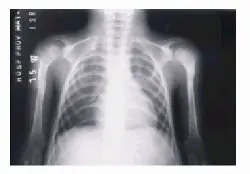

El nombre del síndrome deriva de la palabra griega geras, que significa viejo, y fue acuñado por Gilford en 1904. El síndrome de envejecimiento prematuro, también llamado síndrome de Hutchinson-Gilford o progeria, es un cuadro caracterizado por una aceleración en el proceso natural de envejecimiento, que se produce en estos individuos en edades tempranas de la vida. Este proceso de envejecimiento se produce entre 5 y 10 veces más rápido de lo habitual, por lo que estos pacientes se ven afectados desde la infancia. Son niños sin retraso mental, con baja altura. La esperanza de vida de estos pacientes es corta, nunca supera los 30 años, con un promedio entre los 14 a 15 años. Su muerte ocurre generalmente en la adolescencia, la mayoría de las veces por enfermedades cardiovasculares. Causas e incidencia Actualmente se desconocen con exactitud las causas que aceleran el proceso de envejecimiento, aunque hay estudios que parecen indicar que esta enfermedad podría ser causada por un gen mutante autosómico dominante que haría inestable al núcleo de las células del organismo acelerando el proceso de muerte celular. Lamin A es el nombre del gen recientemente identificado como el causante de algunos tipos de progeria. La función del producto de este gen es desconocido, pero se piensa que estaría involucrado en la supresión del fenotipo de envejecimiento. Al encontrarse alterado, este gen no cumpliría bien su función supresora, fallando en último caso el proceso de frenado del envejecimiento. La progeria sería en este caso una enfermedad genética, lo que no significa que tenga que ser necesariamente una enfermedad hereditaria. La mayoría de los casos se producen por mutaciones esporádicas, es decir mutaciones que se producen en el gen del individuo afectado, y no transmitidas por sus progenitores. La incidencia de la progeria clásica ha sido estimada en 1/8 000 000 de recién nacidos vivos. No se ha evidenciado preferencia por ningún sexo en particular, pero se han comunicado muchos más pacientes de raza blanca (97% de los pacientes afectados). Síntomas La progeria ha llegado a ser una enfermedad de conocimiento público, debido a que sus síntomas, que incluyen adelgazamiento y manchas de la piel, reabsorción de la masa ósea, pérdida de cabello y arteriosclerosis, se asemejan bastante al envejecimiento humano normal. La progeria produce un rápido envejecimiento de los niños, comenzando con una deficiencia en el crecimiento durante el primer año de vida que tiene como resultado cuerpos desproporcionadamente pequeños en relación con el tamaño de sus cabezas. Los niños son delgados y presentan calvicie, cara alargada y arrugada y piel de apariencia envejecida. Los niños con progeria desarrollan aterosclerosis temprana. La esperanza de vida para estos niños, si bien es muy variable, nunca supera los 30 años. La piel es delgada y con escaso tejido celular subcutáneo, las uñas son quebradizas, curvadas, amarillentas e incluso pueden faltar en algunos dedos. La muerte prematura se produce por arteriosclerosis o enfermedad cerebro-vascular y falta de medro. Estos son los principales síntomas característicos de la progeria: * Deficiencia en el crecimiento durante el primer año de vida * Cara alargada y arrugada * Mentón retraído * Ojos saltones y nariz en forma de pico * Calvicie * Pérdida de las pestañas y las cejas * Estatura baja * Cabeza grande para el tamaño de la cara (macrocefalia) * La fontanela (punto blando) permanece abierta * Mandíbula pequeña (micrognatia) * Piel seca, descamativa y delgada * Pecho estrecho * Abdomen abultado * Huesos deformes * Enfermedades degenerativas, como la artritis, propias de la vejez * Rango de movimiento limitado * Retardo en la formación o ausencia de los dientes Diagnóstico El diagnóstico de la progeria es fundamentalmente clínico y se plantea en niños que presentan los signos iniciales de enfermedad entre el primer y segundo año de vida y que manifiestan las características fundamentales de la enfermedad. No existe ninguna prueba que pueda establecer por si misma el diagnóstico definitivo de progeria, pero este puede apoyarse en algunas pruebas bioquímicas, histológicas y radiológicas. Alteraciones radiológicas: cara y cráneo fontanelas permeables, huesos wormianos con fracturas, hipoplasia malar y mandibular, dientes apiñados; hipoplasia clavicular en el tórax, costillas ahusadas; largos identaciones en los huesos, corticales delgadas, metáfisis anchas, coxa valga, coxa plana, genu valgum; en las falanges acro-osteolisis progresiva de las falanges distales; y otros signos como osteoporosis, escoliosis, cuerpos vertebrales en forma de boca de pescado, luxación de cadera, falta de unión de fracturas y pérdida de tejidos blandos. 1- Rayos X de tórax (vista anteroposterior). Osteólisis total de ambas clavículas y de las primeras costillas. Osteólisis parcial de las segundas y terceras costillas. 2- Rayos X de columna lumbosacra (vista lateral). Persistencia de la escotadura en cara anterior de las vértebras dorsales (vértebras en fishmouth). Espondilolistesis de la quinta vértebra lumbar sobre la primera sacra. 3- Rayos X de ambos pies (vista anteroposterior). Osteólisis parcial de falanges distales de ambos pies. 4- Rayos X de pelvis ósea (vista anteroposterior). Coxa valga bilateral. Características histopatológicas: incluyen alteraciones de la piel como áreas de piel normal que alterna con zonas de esclerodermia, la dermis es delgada y presenta zonas de desorganización de fibras colágenas y áreas de hialinización. A nivel del tejido subcutáneo se evidencia pérdida de tejido graso, múltiples anomalías en el hueso, tipo: osteolisis, osteoporosis, displasia esquelética, necrosis avascular de la cabeza femoral, luxación de cadera y fracturas sin resolución. A nivel cardiovascular se encuentran placas ateromatosas, presentes en todos los vasos, pero más prominentes en las arterias coronarias, la aorta y las mesentéricas. Otro hallazgo son las calcificaciones de las válvulas aórtica y mitral, así como signos de fibrosis, isquemia e infarto del miocardio. Alteraciones bioquímicas: el hallazgo más constante en estos pacientes ha sido el aumento en la excreción de ácido hialurónico en la orina, evento que no se ha podido relacionar con trastornos endocrinos ni evento dismetabólico alguno. Complicaciones Debido a que la progeria induce envejecimiento precoz, el organismo de los afectados suele desarrollar las siguientes enfermedades: * Aterosclerosis * Arteriosclerosis * Artritis * Artrosis * Diabetes mellitas * Embolias * Hipercolesterolemia * Hipertensión * Osteoporosis Tratamiento Como se desconocen con exactitud las causas que desencadenan la aceleración de la velocidad de envejecimiento y muerte celular, no existe en la actualidad un tratamiento específico capaz de revertir dicha aceleración. Por lo tanto, tendremos que conformarnos con tratar individualmente cada síntoma o complicación que vaya surgiendo con el proceso natural de la enfermedad; intentando limitar al máximo posible su influencia en la vida de los pacientes. Según los investigadores que hallaron la mutación genética responsable del cuadro, este descubrimiento ofrece la clave para hallar en un futuro la curación, como así también conocer aún más el proceso de envejecimiento normal. Es importante que estos niños desarrollen una vida social lo más normal que se pueda, dentro de sus posibilidades, teniendo en cuenta que el desarrollo de la inteligencia no se ve afectado. Algunas Fotos de Casos de Progeria Fuentes: http://www.cualquiera.com.ar/notas/casos-de-progeria.html http://salud.discapnet.es/Castellano/Salud/Enfermedades/EnfermedadesDiscapacitantes/P/Progeria/Paginas/cover%20progeria.aspx